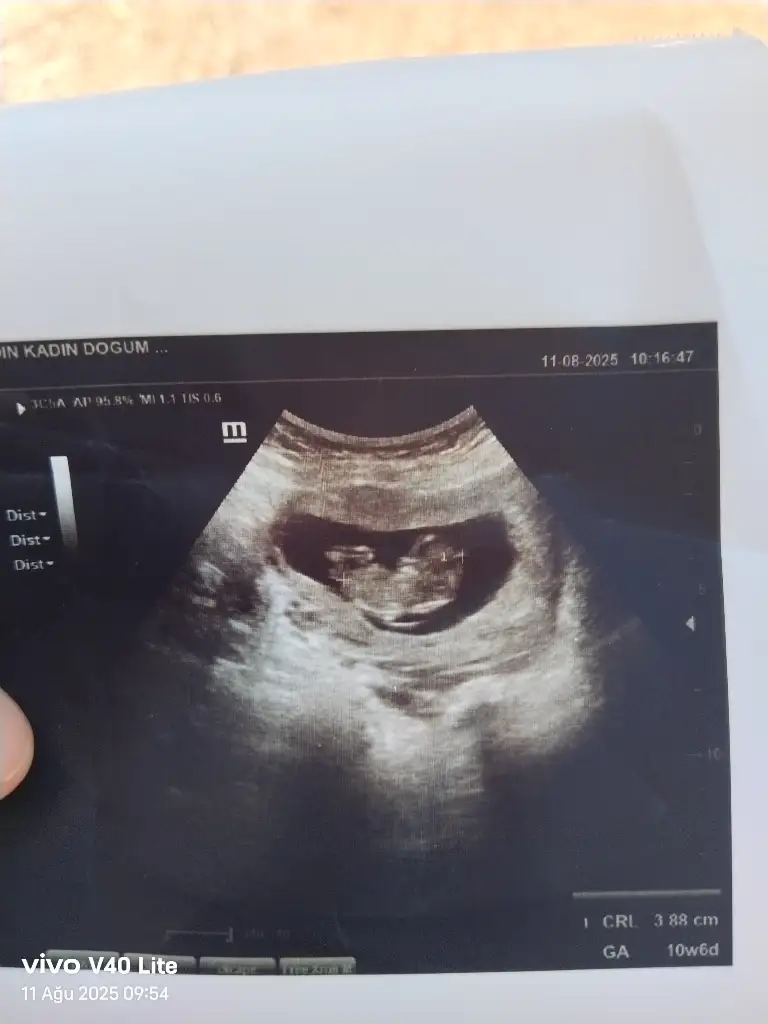

Benim nedir sizce 11+1Erkek bence

Bu bebis de erkek gibi geldi bana ama bilemedim yine de :))Benim nedir sizce 11+1

Ay benimde 12 +1 bana da tahminde bulunabilir misinizKız gördüm sanki, sağlıcakla gelsin

Yüz üstü durmuş sankiAy benimde 12 +1 bana da tahminde bulunabilir misiniz![]()